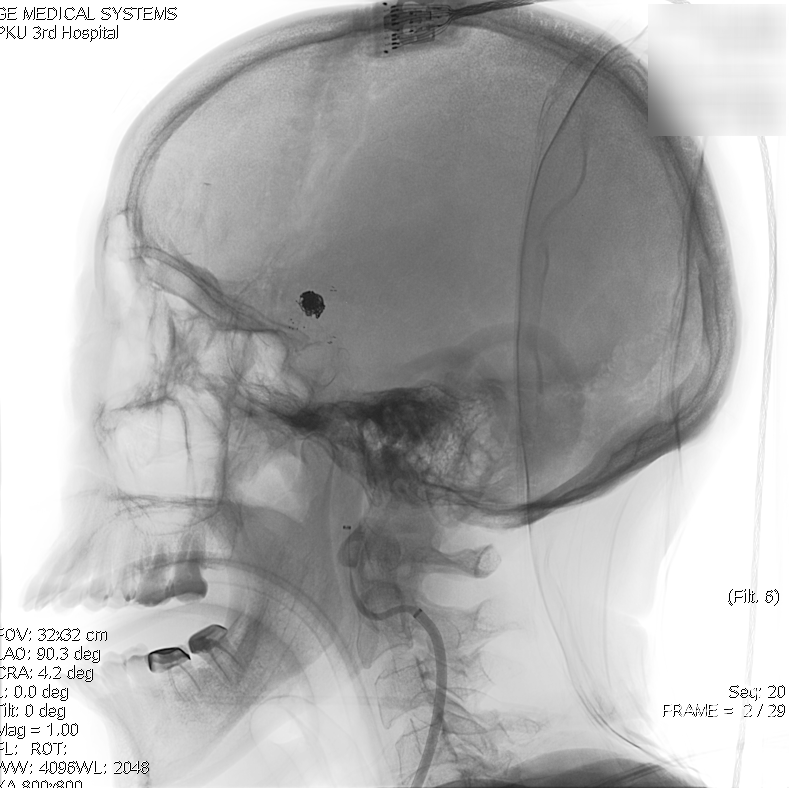

术后正侧位透视

术后三维重建,支架贴壁良好,动脉瘤完全栓塞。